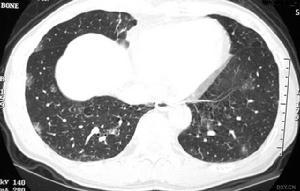

特发性含铁血黄素沉着症(idiopathic pulmomaryhae mosiderosis,IPH)乃一种病因未明,肺内间歇出血的少见疾病。国际上报告200多例,中国报告120余例(到1994年)。肺泡内红细胞破坏后,珠蛋白被吸收,含铁血黄素沉着于肺组织引起反应。由于反复出血可继发缺铁性贫血 。根据反复的咯血,痰中带血,肺内边缘不清的斑点状阴影,及继发的缺铁性贫血可作出初步诊断,通过对痰液,支气管肺泡灌洗液及肺活检中找到吞噬细胞中含蓝色的含铁血黄素并排除心源性淤血性因素后可确诊。[1]